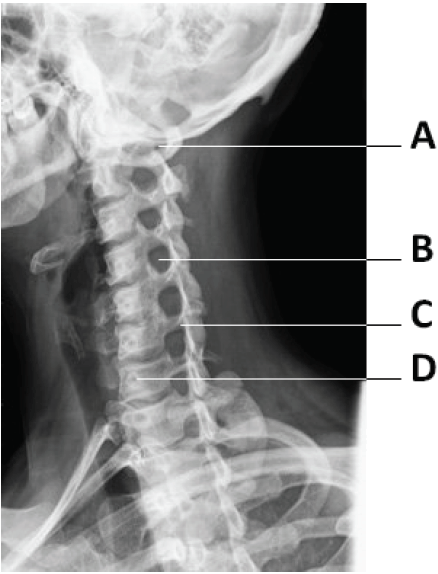

Analise a imagem apresentada na figura a seguir.

Fonte: Bushong (2010, p.298). Adaptado.

Avalie o que se afirma sobre essa imagem.

I. A figura representa o posicionamento oblíquo da coluna e demonstra os forames intervertebrais.

II. A figura mostra uma imagem radiográfica AP da coluna cervical.

III. A figura representa um perfil da coluna com a apresentação das sete vértebras cervicais.

IV. Na figura, A representa o arco posterior e o tubérculo de C1 e em B, o forame intervertebral entre C4 e C5.

Está correto apenas o que se afirma em